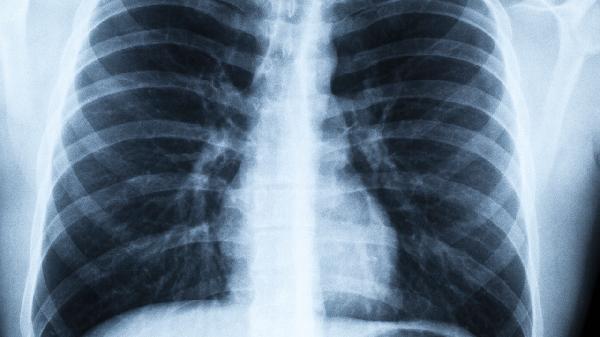

5、长期管理包括定期复查、避免诱因和健康生活方式。定期复查如胸部X线、肺功能检查可监测病情变化;避免诱因如戒烟、避免剧烈运动可减少复发风险;健康生活方式如均衡饮食、适量运动可提高整体健康水平。